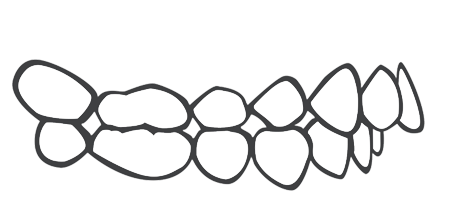

牙列间隙过大

深覆盖

牙列拥挤

深覆颌

开颌

前牙反颌